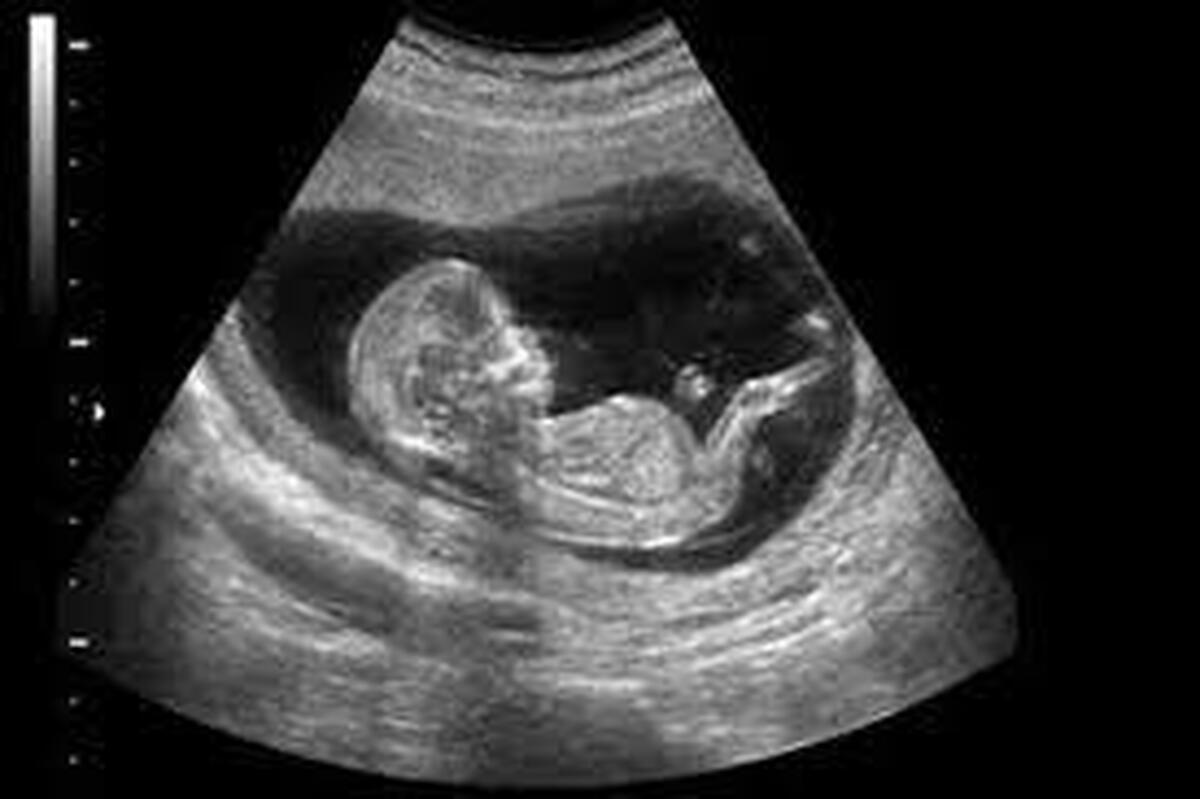

آیا فعالیت بدنی در دوران بارداری برای جنین خطرناک است؟